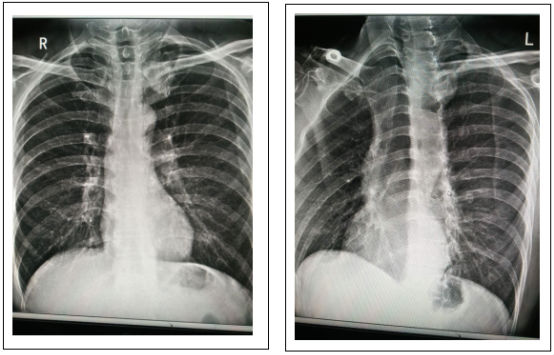

病史:腹股沟斜疝入院手术,无呼吸道症状,术前DR胸部拍片检查,胸片提示左肺上野内带局限性密度增高,并与左侧胸锁关节及钙化的第一肋软骨阴影重叠。正位胸片很难确定病变所在,容易遗漏。追问病史,患者于三个月前在当地卫生院体检拍胸片(当地卫生院使用的是常规x光机)未见异常。

在我院用DR动态透视转体观察:明确左肺上叶分叶状球形病灶,我院影像诊断为肺肿瘤,次日,患者到市医院CT增强扫描确诊左上肺癌。

病人因腹股沟斜疝入院,无呼吸道症状,手术前DR胸部拍片检查,胸片提示左肺上野内带局限性密度增高,并与左侧胸锁关节及钙化的第一肋软骨阴影重叠。由于正位胸片很难确定病变所在,无法准确诊断,甚至容易漏诊。为了确保能够确定病变所在,准确诊断,我们采用动态DR透视观察功能,经透视过程中转体观察:明确左肺上叶39X32㎡分叶状球形病灶,并在透视下高清点片,获得诊断依据。我院影像诊断考虑肺肿瘤,建议CT扫描。次日、患者前往市医院进行CT增强扫描,确诊为左上肺癌。并及时入院治疗。